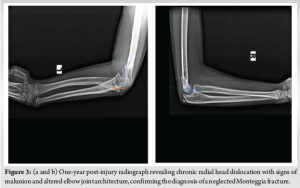

On examination, the patient had complete flexion and extension of the left elbow which was compared to the opposite side. Pain on terminal flexion and extension was noted. The patient had a reduction of pronation and supination of the left elbow compared to the opposite side. The wrist joint was duly examined and was found to be normal. Radiographs were taken of both elbow joints, and the patient was diagnosed to have a neglected left Monteggia fracture (Bado type IV) with a malunited radial head (Fig. 3).

A computed tomography (CT) of the left elbow was ordered with due stress on 3D reconstruction to visualise the deformity from different planes. The parents were counselled regarding the need for surgery to correct the deformity and to restore the appropriate radial head alignment. Using the CT 3D reconstruction video (Fig. 4a), a plan was formulated to form a 3D model of the malunited radial head with its articulation at the radio-ulnar and radio-humeral joint. The 3D reconstruction models were brought to life (Fig. 4b), and with it, our osteotomy methodology was envisioned.